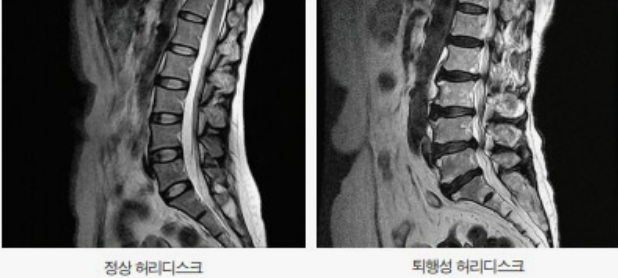

허리디스크란?

허리 사이에 있는 디스크가 외부의 충격이나 노화로 인한 퇴행성 변화로 점점 압박을 받아 밀려 나오는 것을 말합니다.